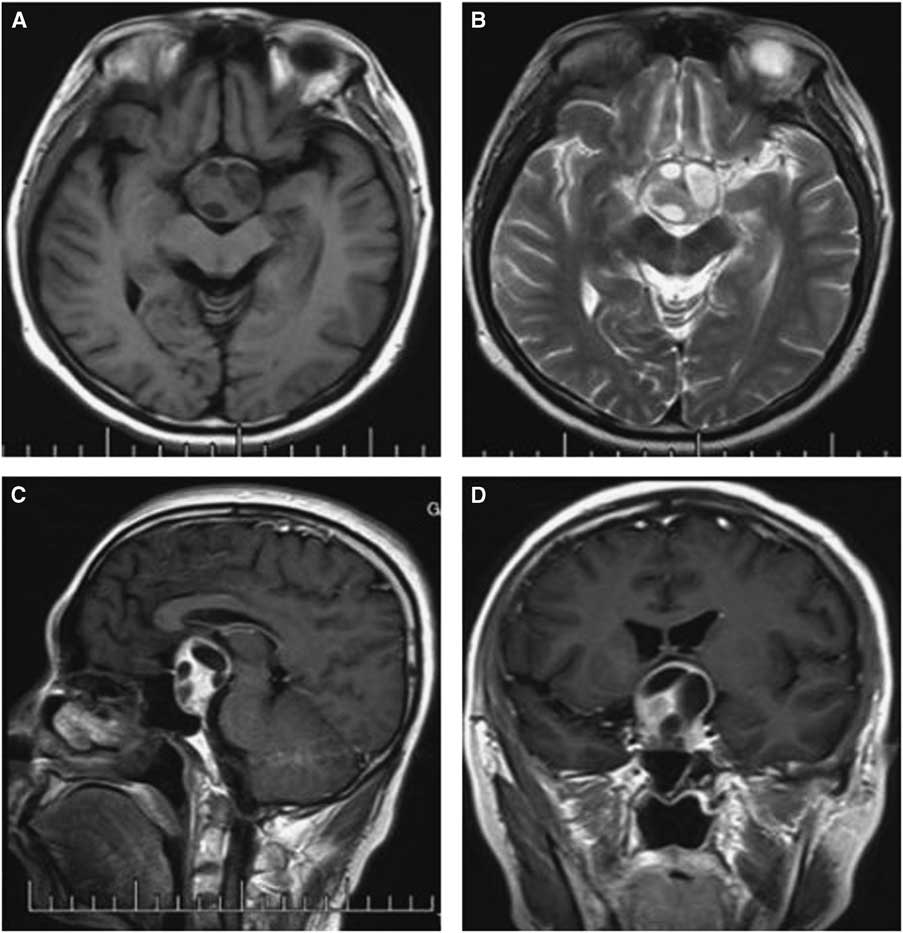

Computed tomography and MRI were performed for each patient preoperatively. Of the PAs, two were microadenomas diagnosed on dynamic contrast-enhanced scan of the sellar region with MRI. The others were macroadenomas. The tumors were mainly located in the intra- and suprasellar areas, except for four cases that involved the parasellar region. Among these cases, two were grade 3 on the Knops scale, whereas the other two were grade 4. The typical imaging of PA associated with RCC was that a cyst-like signal with no contrast enhancement was indicated on MRI with an obvious PA, and the cyst was usually enclosed by the PA or adjacent to the adenoma, as shown in case 3 (Figure 1). However, it was occasionally difficult to identify the two different signal intensities between the PA and RCC, as indicated in case 1 (Figure 2). The 15 patients were all initially diagnosed with PAs or PAs with cystic change or apoplexy of PAs.

Figure 1 Preoperative and postoperative MRI scans of case 3. Axial T2-weighted (A) images showing an isointense mass in the sellar region with multicystic lesions inside; Contrast-enhanced sagittal (B) and coronal (C) images show obvious enhancement of the solid mass and no changes in the cysts, with the tumor extending into the suprasellar area. The postoperative images show the tumor was totally removed and there was a hemorrhage at the site of the operation (D-F).